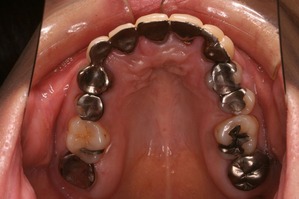

上から見ると、前歯はブリッジとなっており、左右1本づつ歯が欠損しております。

つまり、歯を抜いたのが左右1本ずつで、残りの歯をけずってブリッジにしております。